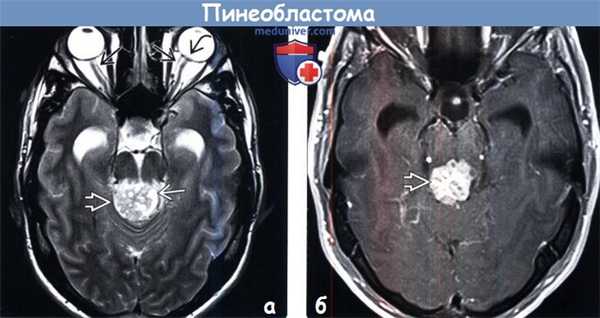

(а) МРТ, Т2-ВИ: у этого же пациента определяется, что объемное образование имеет неоднородно гиперинтенсивный сигнал. В структуре опухоли визуализируются множественные кистозные компоненты.

Наблюдается отек диска зрительного нерва с протрузией головки зрительного нерва и дилатацией оболочек зрительного нерва.

(б) МРТ, постконтрастное Т1-ВИ, режим подавления сигнала от жира: у того же пациента определяется высокоинтенсивное, но гетерогенное контрастирование объемного образования.

Предоперационный дифференциальный диагноз: опухоль паренхимы эпифиза промежуточной дифференцировки или папиллярная опухоль пинеальной области.

Окончательный диа гноз - пинеобластома IV степени злокачественности по классификации ВОЗ (grade IV).